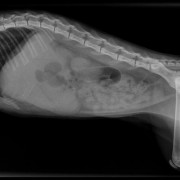

De malteser Daisy, een teefje van 10 jaar, kwam op 27 mei 2010 met blaasklachten op de praktijk. Dit is niet de eerste keer; in 2008 heeft zij ook al blaasproblemen gehad. Bij het onderzoek blijft op de röntgenfoto dat er een groot aantal grote en kleine stenen in de blaas aanwezig zijn. Deze stenen irriteren de blaaswand wat een blaasontsteking en pijn geeft. Ook kunnen deze stenen gemakkelijk in de plasbuis vastlopen waardoor het plassen bemoeilijkt wordt of zelfs helemaal niet meer lukt. We hebben Daisy operatief van deze stenen af geholpen. Daarna ging het  stukken beter. Daisy heeft zelf nog enkele kleine steentjes uitgeplast. Ze krijgt speciaal dieet om de vorming van deze stenen in de toekomst te voorkomen.

Meerdere blaastenen zichtbaar op de röntgenfoto (linksonder)